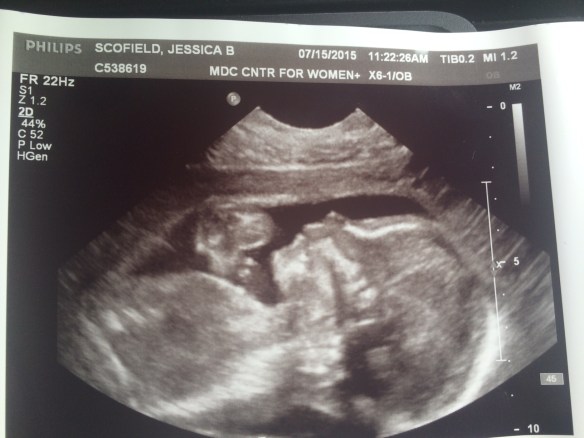

I can’t wait to meet him. Have I shared that my guess is it’s a boy?

Which probably means it’s a girl.